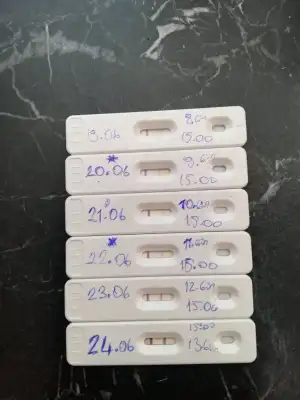

Artık Temmuzda benim denemeler :)

Artık Temmuzda benim denemeler :)